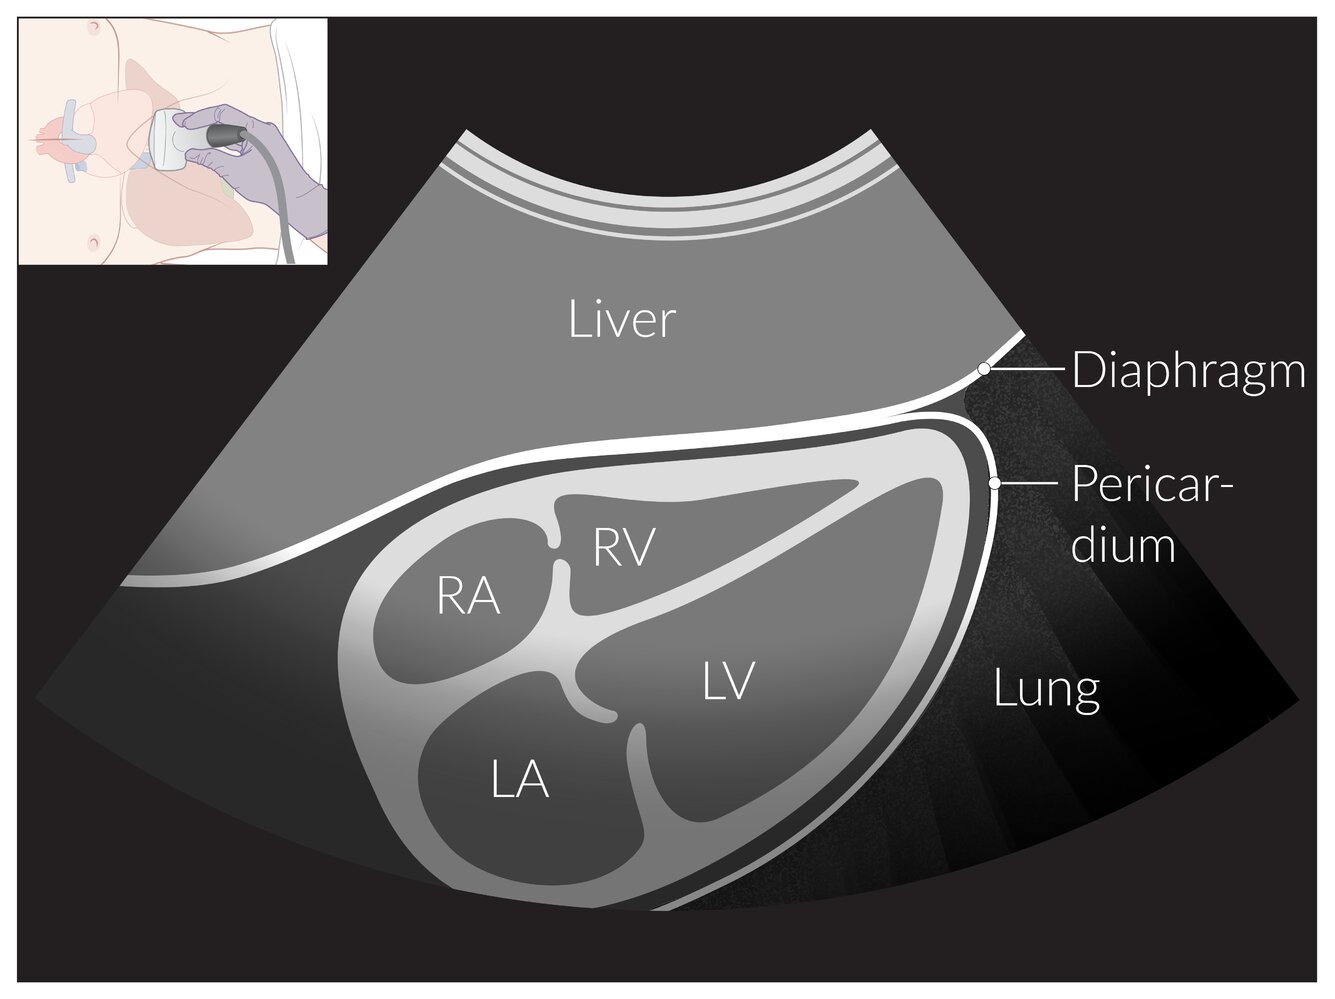

Transthoracic echocardiography (TTE) [1][2]

• Description: : noninvasive ultrasound examination of the heart (most frequently used cardiologic imaging modality)

• Common techniques

• Two-dimensional TTE

• Three-dimensional TTE

• Doppler mode

• Stress echocardiography

• Contrast echocardiography

• Common uses

• Initial evaluation of pathological heart murmurs [3]

• Assessment of valvular function by determining: [4]

• Assessment of myocardial contractility, e.g., in heart failure, myocardial infarction, pulmonary embolism

• Evaluation of other pathologies, e.g., septal defects, aneurysms, thrombi, vegetations, pericardial effusions